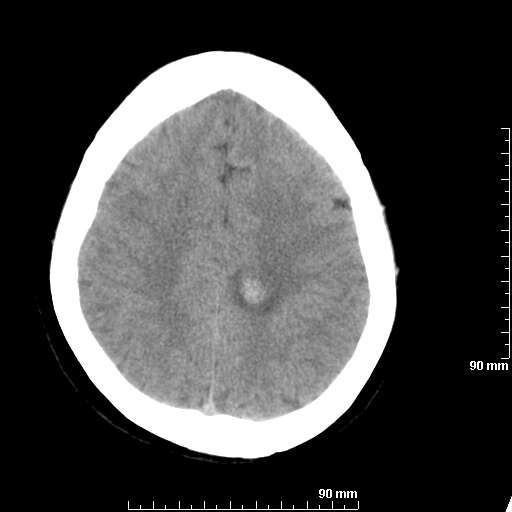

[维修案例解析] 大家猜猜看,这个伪影是怎样产生的.

二马日王 显示全部楼层 发表于 2011-6-9 18:12:55 |阅读模式

我院西门子单排CT由于一零件受损而产生的伪影.

哈哈,都不是。是虑线器fiter裂损。大家没想到吧。

哦,跟脑出血有点像哦

形状不规则,边缘模糊。比较特殊的一种伪影哈!

这种伪影很常见!伪影应该是在视野的中心的。

西门子的虑线器fiter裂损这才是很难见的问题,GE的最常见

虑线器老化,中间崩裂一块掉了